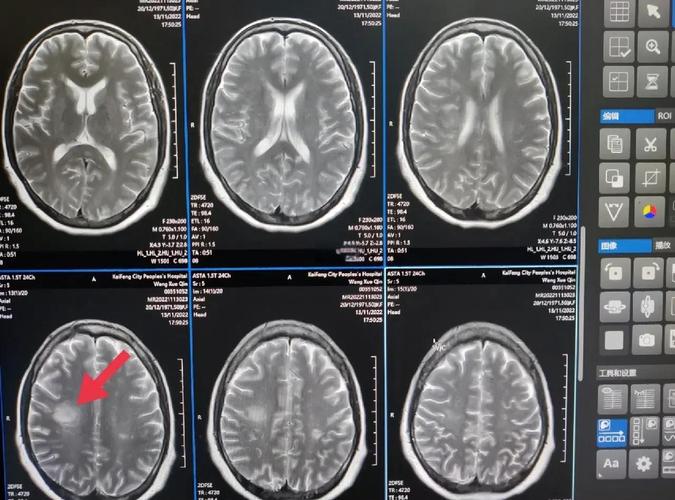

- 脑实质密度改变: 在发病12-24小时后,缺血坏死的脑组织会因为细胞破坏、蛋白质含量增高等原因,在CT上显示出低密度区域(图像上颜色变暗),这时,梗塞的部位、范围和形态就比较清晰了。

(图片来源网络,侵删)- MRI(磁共振)是更优的选择: 对于超早期的脑梗塞(发病6小时内),弥散加权成像(DWI)序列的MRI几乎可以立即发现梗塞灶,比CT敏感得多,如果CT结果正常但临床症状高度怀疑脑梗,医生会建议尽快做头颅MRI检查以明确诊断。